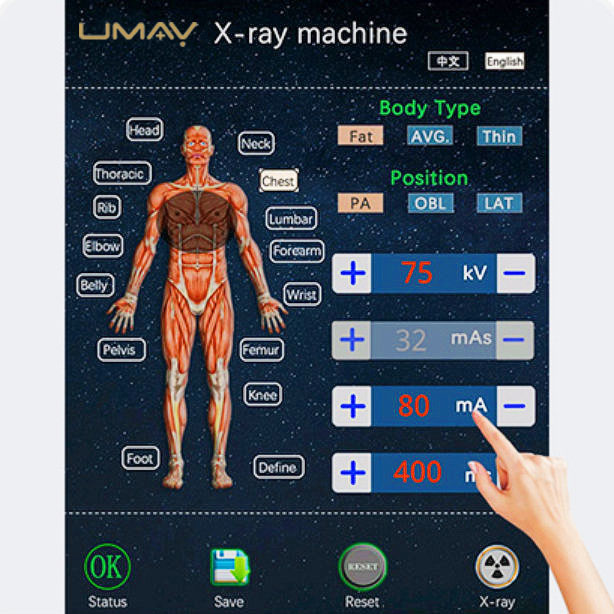

- 10.4-inch LCD Touchscreen

- 14 Pre-Set Imaging Parameters

- User-Friendly Design